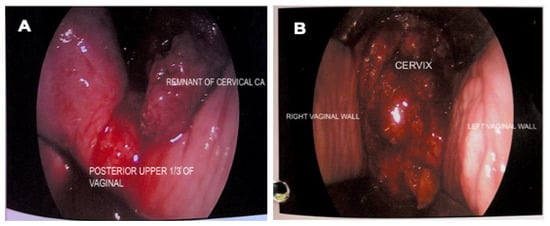

An examination under anaesthesia noted normal vulva and smooth vagina with no nodularity. However, a small raw area (1 × 1 cm) was noted at the upper 1/3 of the vagina (Figure 2A). An exophytic growth of 4 × 4 cm, occupied 9 to 5 o’clock position of the friable cervix which bled on touch (Figure 2B). Cystoscopy noted normal bladder mucosa and no evidence of tumour invasion. The assessment showed clinical staging of the cervical cancer as stage 2A. Histopathological examination of the upper 1/3 posterior vagina and cervix was consistent with human papillomavirus (HPV)-associated keratinizing squamous cell carcinoma (Figure 3). The tumour cells showed block positivity towards P16 immunohistochemical stains (not shown).

Figure 3. Pathological examination of the upper 1/3 posterior vagina and cervix. Hematoxylin and eosin staining showing (A) cell carcinoma infiltration (100× magnification) and (B) cells with enlarged hyperchromatic nuclei, inconspicuous nucleoli and moderate eosinophilic cytoplasm. Mitotic activities are brisk (arrow) (400× magnification).